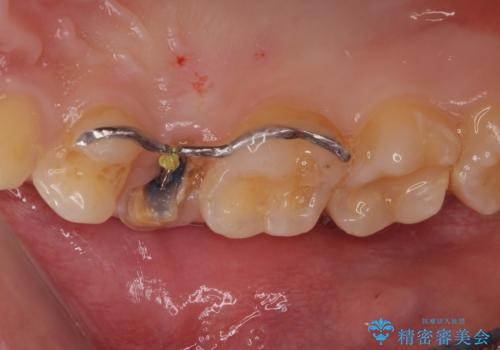

右上の被せものを除去したところ、中で歯が割れていたため、部分矯正で引っ張り出すことになりました。

・約3か月ほど引っ張り出します。

・両どなりの歯に一時的にワイヤーを接着します。